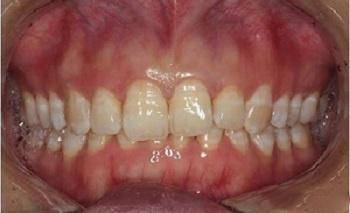

▍ 异常8:深咬合(深覆、深覆盖)

孩子牙齿不齐,要等换牙后再矫治吗?#雅悦齿科#

第八种情况是深咬合,深咬合的危害包括:上腭软组织创伤、增加牙外伤风险、限制下颌的位置,影响关节发育等。